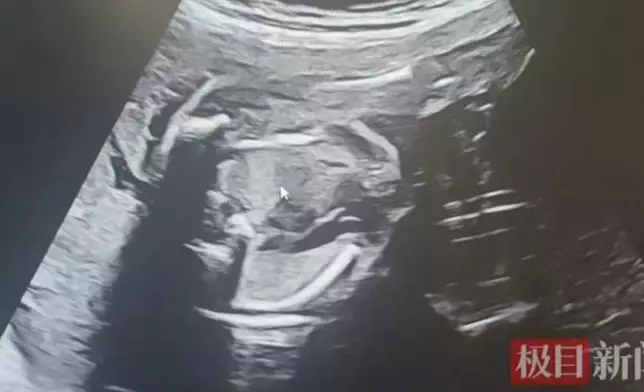

初期檢查尚算平穩,直至孕25周,孟女士突感腹部脹痛難忍,急赴醫院求診。超聲波結果顯示,一名胎兒羊水過多,另一名則幾近枯竭,確診為典型雙胎輸血綜合症。產科主任醫生周潔瓊解釋,共用胎盤上出現異常血管吻合支,導致供血兒血液持續流向受血兒,打破血液平衡,若不及時處理,兩名胎兒均有生命危險。